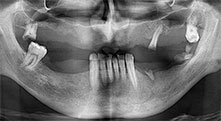

El Dr. Emanuel Bratu, catedrático con doble doctorado, es cirujano oral, cirujano maxilar y protésico y dirige los departamentos de implantología de dos universidades en Rumanía. Además, es el propietario de una reputada clínica privada en Timisoara y también se le considera una autoridad internacional en el campo de la investigación. En la entrevista, el Dr. Bratu explica las razones por las que el equipo piezoquirúrgico Piezomed de W&H y, en particular, sus dos sierras patentadas, se han convertido en elementos imprescindibles en las intervenciones óseas que se llevan a cabo en el campo de la odontología.

Bratu: Utilizamos los insertos de forma rutinaria para la extracción de injertos óseos y la ranuración de las crestas alveolares. También utilizamos las Piezomed B6/B7 para practicar osteotomías en dientes retenidos y no retiramos implantes que pueden conservarse. Todas estas son indicaciones que requieren cortes profundos y limpios.

Bratu: Preferimos realizar las osteotomías en la línea oblicua externa de la cara posterior del maxilar inferior, y no en la región situada entre los orificios. Tras realizar una incisión en los tejidos blandos, utilizamos las nuevas sierras para definir el contorno de la osteotomía. De este modo, conseguimos una preparación completa en prácticamente el 80 por ciento de los casos. Por otro lado, en algunas ocasiones también utilizamos otros insertos piezoquirúrgicos, así como un cincel para mover el injerto. Para nosotros, esta es una técnica de intervención muy eficaz.

Bratu: Nos gusta utilizar la técnica de sándwich para realizar aumentos en la cara lateral del maxilar inferior. En este procedimiento, se utiliza la sierra piezoquirúrgica para preparar una tapa ósea, mientras que el fragmento crestal se fija con microtornillos. Entre medias, colocamos una combinación de hueso autólogo y material óseo adicional xenógeno. Y con ello obtenemos un rendimiento muy fiable. Asimismo, en los ranurados de la cresta alveolar del maxilar inferior, nunca se puede prescindir de cortes verticales suficientemente dimensionados, pues, de lo contrario, los huesos pueden fracturarse fácilmente.